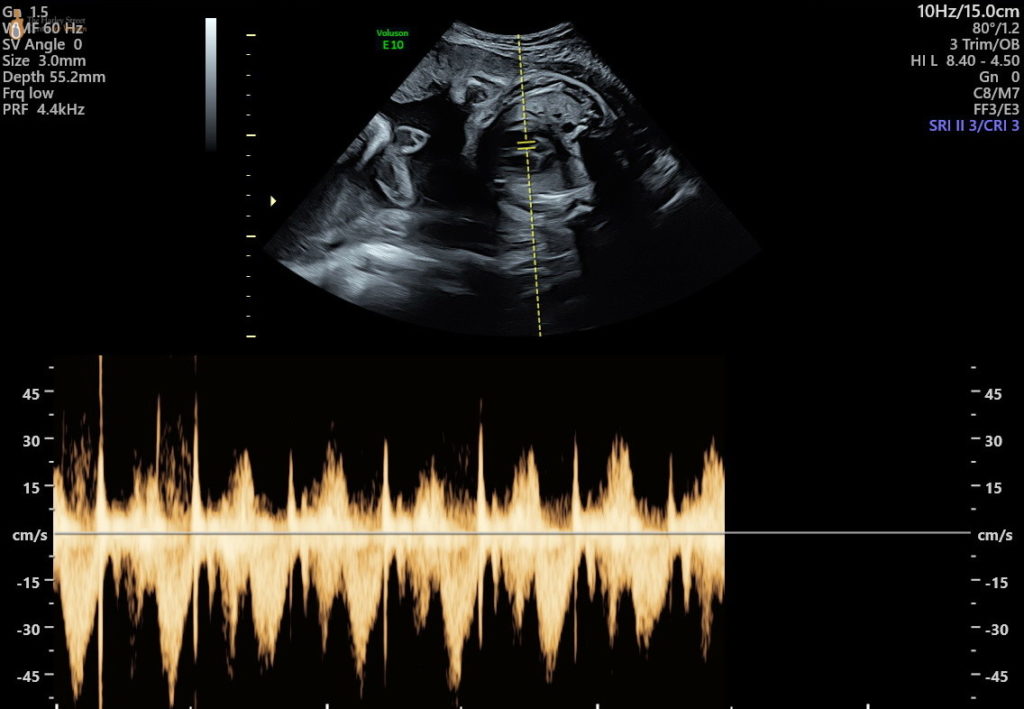

Her message a few hours ago said, “all is very well”. “The due date has been pushed to July 29”. It still fascinates me they can get that level of accuracy (and adjust it as needed). We’ll see. They also told her to rest more. It feels like she just sleeps and eats at the moment so I have no idea how she could do more resting. I think she’ll struggle to get back to work in a few weeks. It worries me. She assures me she’ll readjust just fine.

It’s been an emotional day for her and she’s rightfully elated and now has some peace of mind. She’s “overwhelmed at the notion of all this happening in her body”. I can see that, especially for a first-timer. But I don’t feel anything new. She sent me some scans. I can’t make sense of them. I said, “nothing,” when she asked how I was feeling (after seeing the scans). She said I was being cold. But it’s like watching a great film at the theatre and sending me a picture of it, expecting the same emotional response of the experience you just had.